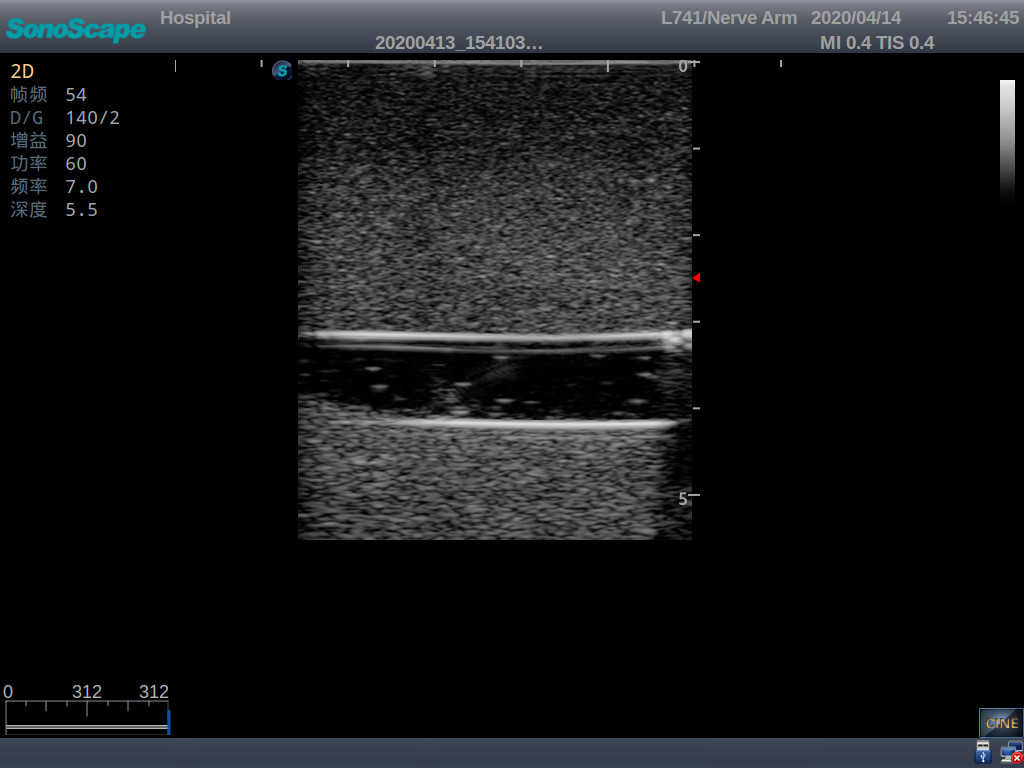

PICC Ultrasound Training Model

Model TYE1510.1

Outline

It is a model covering up from lobulus auriculae plane to the umbilical plane, and it has anatomical structures like clavicle, rib, sternocleidomastoid, jugular vein and basilic vein.

1)   Made of high molecular polymer ultrasound material, close to the real skin

2)   It can be used by real ultrasound machines

3)   Clear and real images of the tissues and organs (basilic vein and superior vena cava)

5)   Observe the guide wire marches

6)   Detect whether the catheter is properly placed